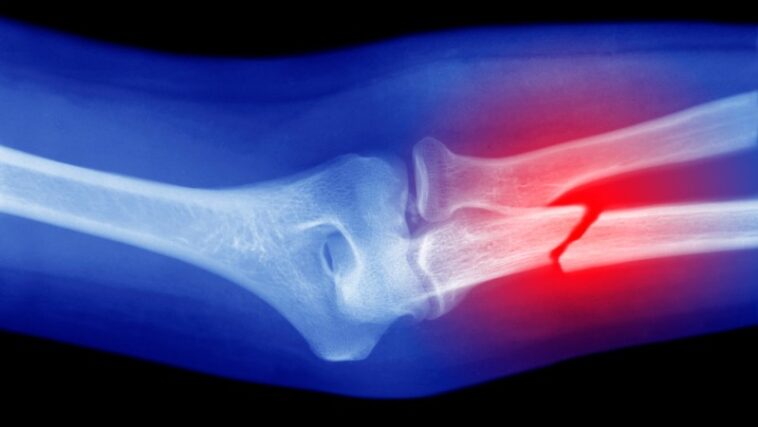

Un dispositif portable peut appliquer des greffes osseuses synthétiques directement sur le site d'un défaut ou d'une blessure sans avoir besoin d'imagerie ou de fabrication préalable.

Les chercheurs ont démontré la technologie en modifiant un pistolet à colle chaude pour imprimer en 3D le matériau directement sur les fractures osseuses chez les lapins. Au lieu d'utiliser un bâton de colle ordinaire, ils ont utilisé une «biose» spécialement fabriquée, l'équipe rapporte le 5 septembre Appareil.

Lee et ses collègues ont testé le pistolet à colle et la biose des fractures osseuses fémorales chez les lapins. En comparant les résultats des lapins recevant la thérapie avec un groupe témoin recevant du ciment osseux ordinaire, l'équipe a constaté que le premier groupe avait une meilleure guérison et régénération du tissu osseux. Les animaux n'ont également montré aucun signe d'infection au cours des 12 semaines suivant la chirurgie.